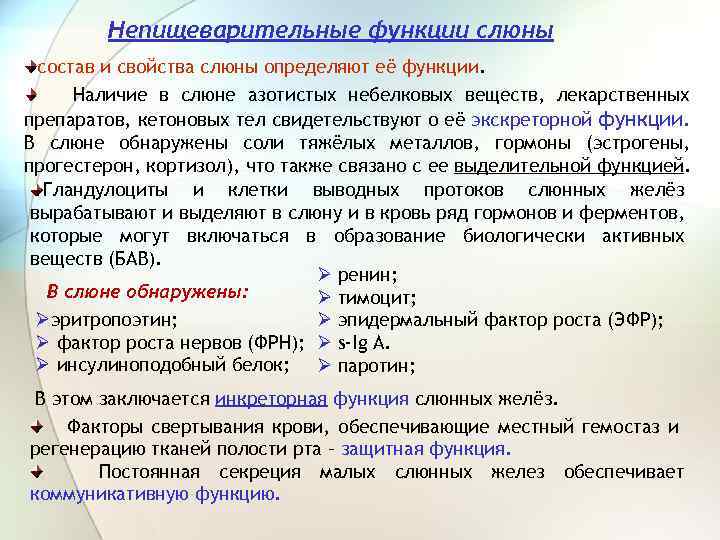

Непищеварительные функции слюны состав и свойства слюны определяют её функции. Наличие в слюне азотистых небелковых веществ, лекарственных препаратов, кетоновых тел свидетельствуют о её экскреторной функции. В слюне обнаружены соли тяжёлых металлов, гормоны (эстрогены, прогестерон, кортизол), что также связано с ее выделительной функцией. Гландулоциты и клетки выводных протоков слюнных желёз вырабатывают и выделяют в слюну и в кровь ряд гормонов и ферментов, которые могут включаться в образование биологически активных веществ (БАВ). Ø ренин; В слюне обнаружены: Ø тимоцит; Øэритропоэтин; Ø эпидермальный фактор роста (ЭФР); Ø фактор роста нервов (ФРН); Ø s-Ig А. Ø инсулиноподобный белок; Ø паротин; В этом заключается инкреторная функция слюнных желёз. Факторы свертывания крови, обеспечивающие местный гемостаз и регенерацию тканей полости рта – защитная функция. Постоянная секреция малых слюнных желез обеспечивает коммуникативную функцию.